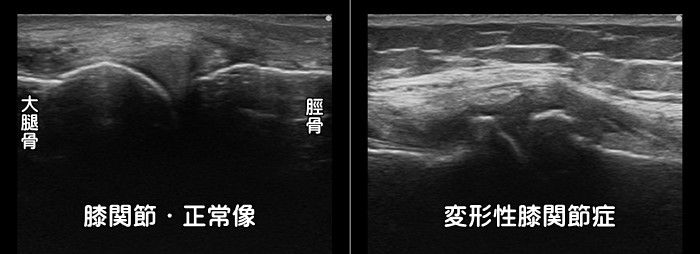

変形性膝関節症

膝の内側の痛みがあれば変形性膝関節症を疑います。軟骨がすり減り、骨が変形します。

エコー検査では変形の有無・炎症の有無を確認できます。